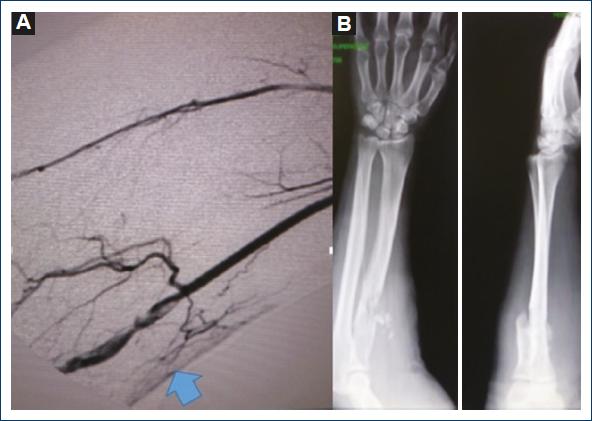

Patient with a case of gunshot wound to the right arm that occurred 1 month before. Since then, he reported paraesthesia in the fingers of his right hand and a drop in temperature. He was assessed at a family medicine unit in a community in Oaxaca and sent to a hospital in Mexico City. The patient was seen at the outpatient clinic of the hospital, where he was referred to the orthopedic service for a suspected fracture of the arm. On reviewing the orthopedic films, the patient was referred to the angiology service, which, on physical examination, observed gunshot wounds in the upper third of the external lateral face of the right forearm, healed as an entrance wound with an exit wound in the lower third of the internal lateral face of the arm with a healed wound. It also revealed increased volume in the elbow with ecchymosis, absence of radial and ulnar pulses, hand pallor, and distal hypothermia (Fig. 1). Doppler and duplex ultrasound was performed, where a total section of the humeral artery with collateral flow was reported. The patient was admitted for arteriography, which reported a lesion of the right humeral artery with flow through collateral circulation, permeable ulnar and interosseous arteries, and absence of flow of the radial artery (Fig. 2). A vascular exploration was scheduled for an inverted S incision on the humeral artery with extension to the forearm, locating extensive hematoma infiltrated in muscle tissue, humeral artery with irregularities in its wall, secondary to firearm burns, 50% laceration of the arterial wall with intra luminal hematoma without palpable flow (Fig. 3). After verifying good proximal humeral flow by thrombectomy with Fogarty catheter 4 and distal with Fogarty catheter 3 with excellent reflux of the distal humeral artery, a reversed saphenous vein graft was placed. Once the procedure was finished, the patient recovered proximal and distal pulses and was sent to the orthopedic unit to continue management of the bone lesion (Fig. 4). Post-operative management continued with unfractionated heparin with a timetable after discharge from the orthopedic unit and was managed with platelet antiaggregants for 3 months. Patient's evolution was satisfactory, medication was suspended, and he was discharged due to improvement.

Figure 2 A: arteriography of the humeral artery with occlusion and lesion of the intima with collateral circulation. B: fracture of the upper third of the right radius.